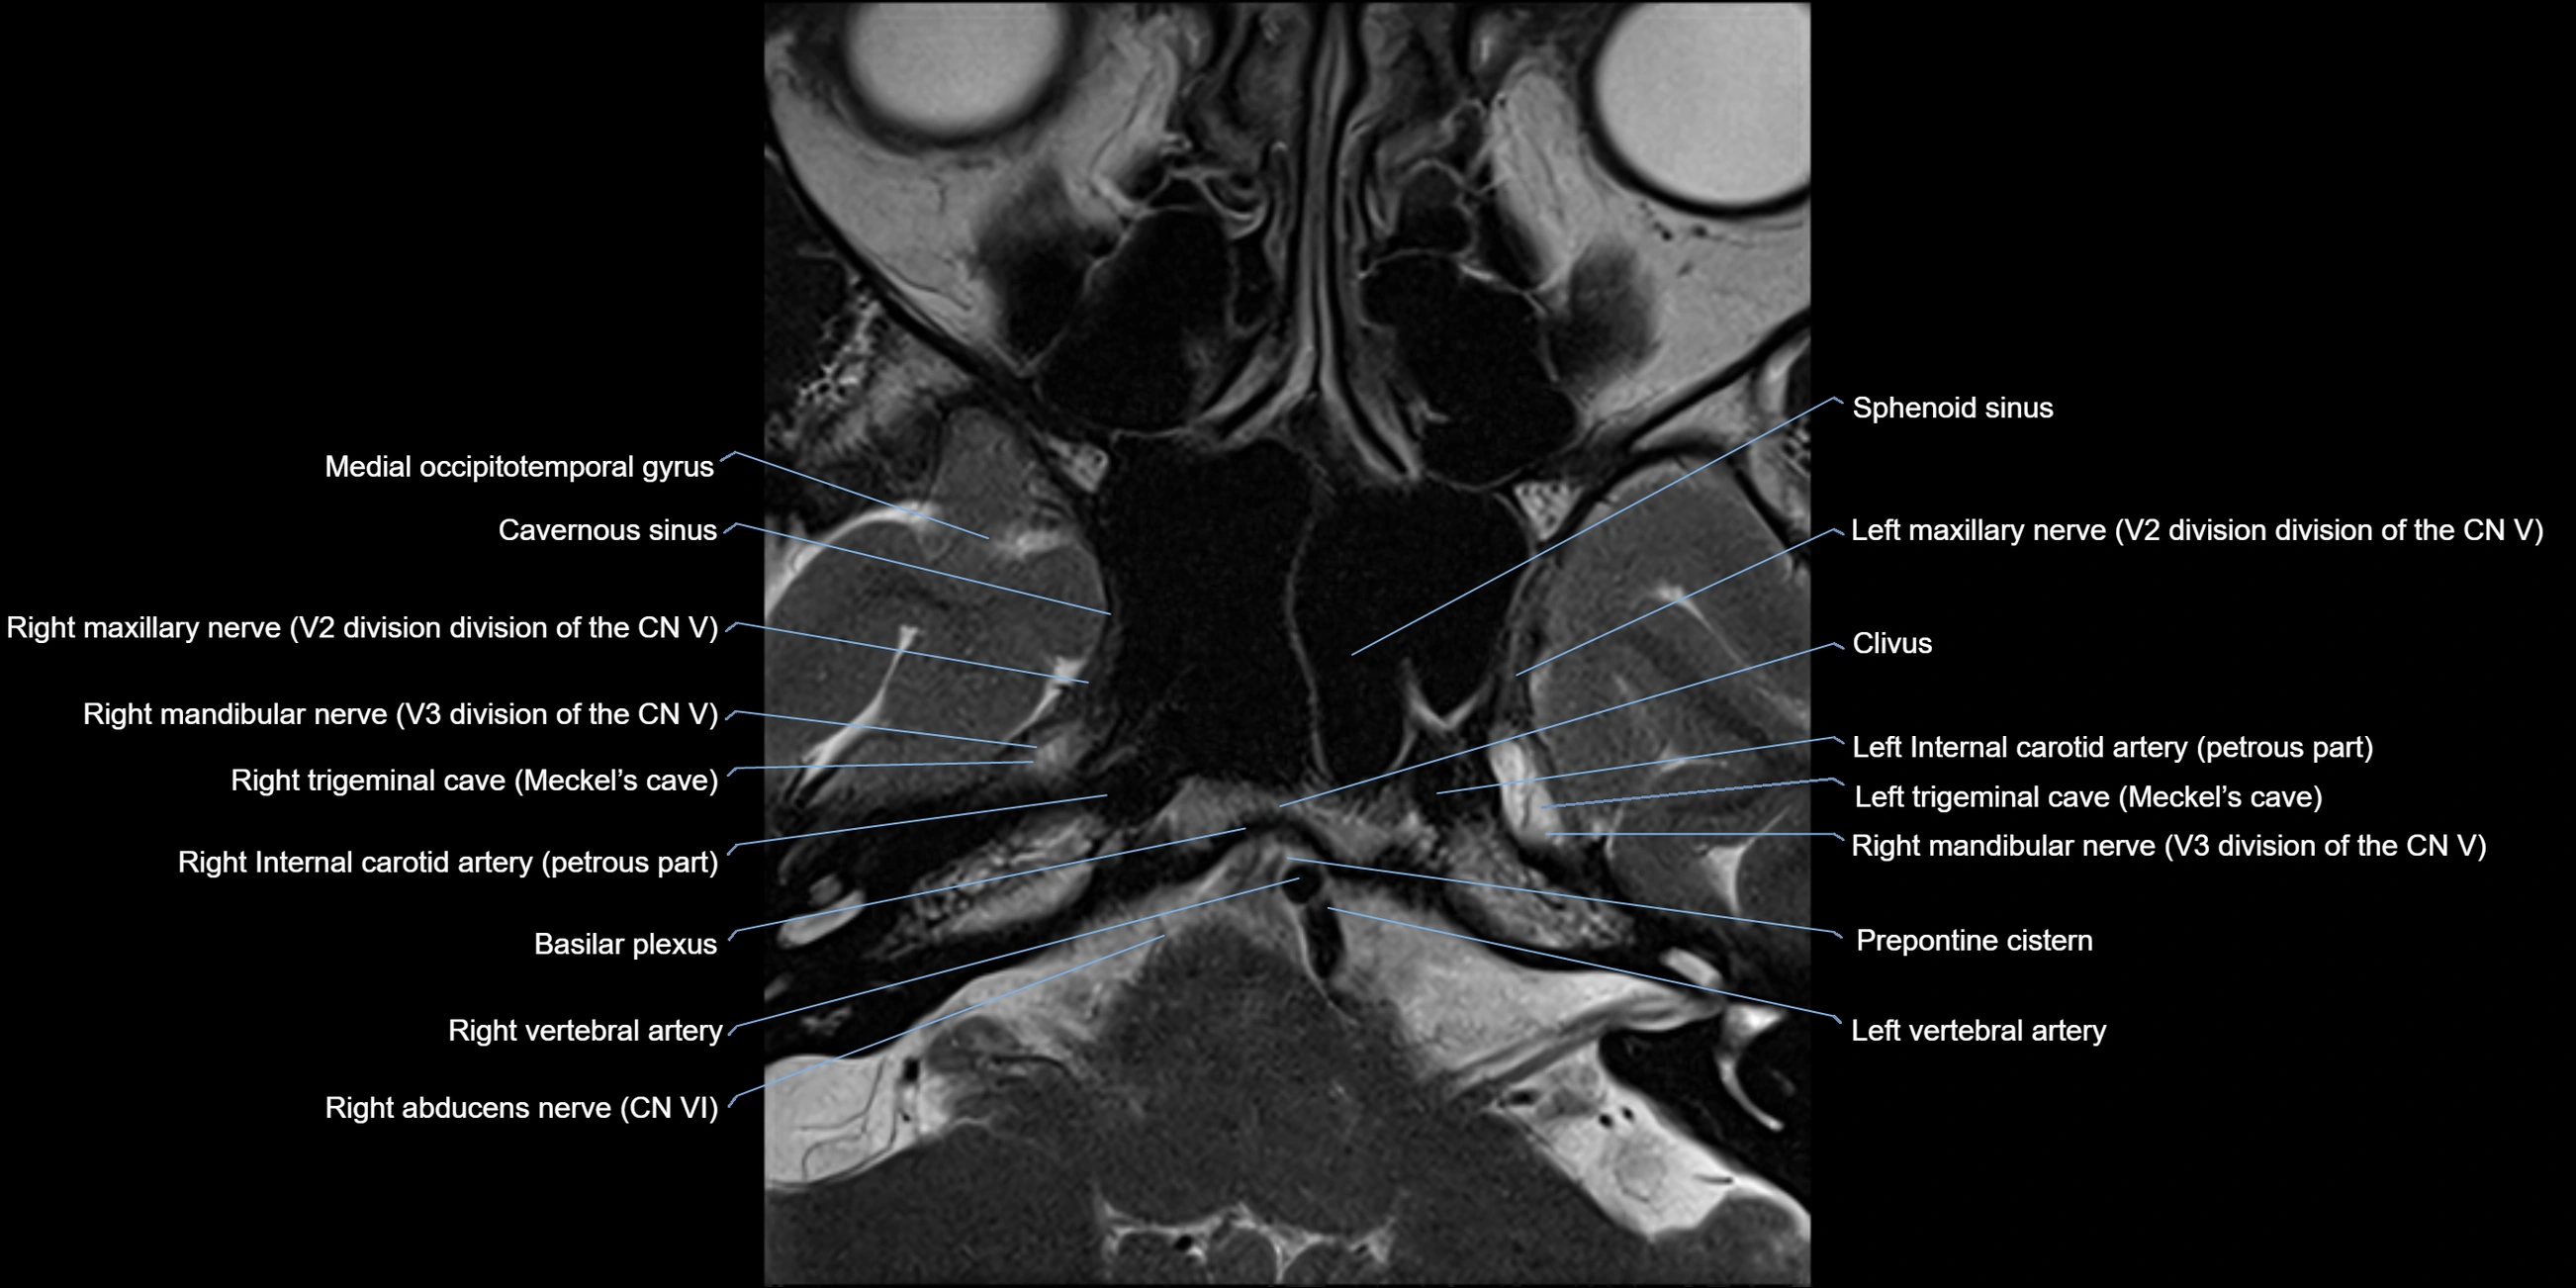

MRI Appearance

The abducens nerve is a small, thin, linear structure

Best visualized on high-resolution T2-weighted 3D MRI sequences (e.g., FIESTA or CISS)

Seen as a hypointense (dark) line running from the brainstem at the pontomedullary junction, traversing the prepontine cistern, and entering Dorello’s canal under the petrosphenoidal ligament, then into the cavernous sinus, and finally the orbit

May be challenging to visualize in standard MRI due to its small size

Pathology may be inferred by absence, displacement, or enhancement of the nerve

MRI images